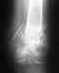

Здравствуйте! Меня зовут Наталья, мне 39лет, в апреле 2006г у меня был закрытый оскольчатый перелом средней трети левой бедренной кости со смещением. Был произведен остеосинтез титановым штифтом 19.04.06. Заключение на 03.09.09 - замедленный консолидирующий оскольчатый перелом. Регионарный остеопороз нижнй трети бедренной кости. Артроз тазобедренного и коленного суставов 1-2 ст. Постоянные боли в бедре. 1. Можно ли удалить частично металлоконструкции для стимуляции остегенеза в месте перелома? (Мой рост - 156, вес -39. Анализ крови (ед.СИ): гемогл - 90, эритроц - 2,8, цвет.роказат - 0,90, СОИ - 30, анизоцитоз +, пойкилоцитоз +, полихроматофилия - гипохр.умерен) Мне отказано МСЭК в продлени инвалидности, мотивируя тем, что перелом сросшийся. 2. Можно ли считать, что перелом сросся?